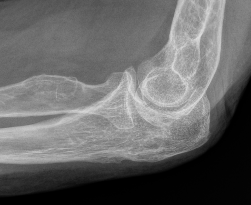

Mayo Classification

A: Non comminuted

B: Comminuted

| Type I | Type II | Type III |

|---|---|---|

| Minimally displaced | Displaced | Trans-olecranon fracture dislocation |

| 10% | 85% | 5% |